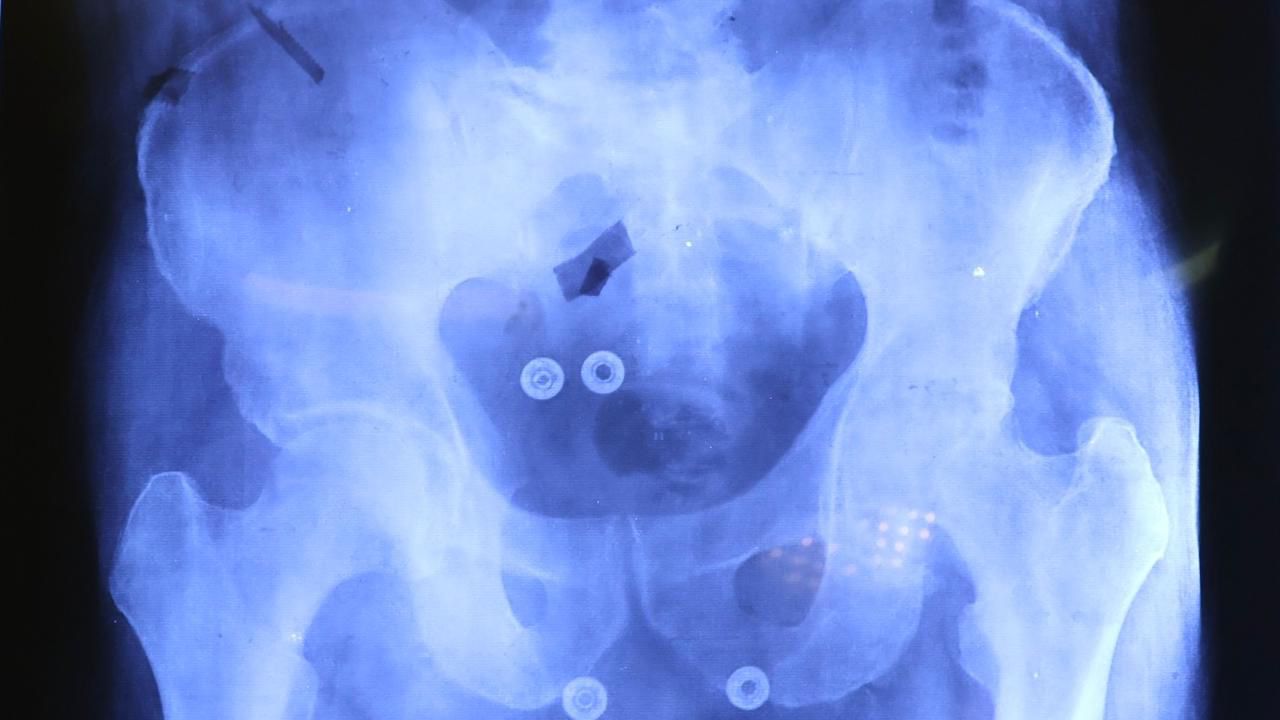

En un esfuerzo conjunto, el Sistema Estatal para el Desarrollo Integral de la Familia (SEDIF), la Beneficencia Pública del Gobierno de México, IMSS-Bienestar y la Secretaría de Salud, iniciaron las cirugías de prótesis de cadera y rodilla para pacientes mayores de 60 años. Durante el fin de semana se realizaron las primeras tres intervenciones quirúrgicas que marcan el comienzo de una serie de procedimientos que buscan mejorar la calidad de vida de los beneficiarios.

El equipo de cirujanos del IMSS- Bienestar comentó que la meta de las operaciones de cadera y rodilla, es que las y los pacientes recuperen la movilidad y funcionalidad; se reduzca el dolor y limitaciones físicas, así como mejorar la calidad de vida y oportunidades de desarrollo personal.

José Francisco González y Javier Sandoval Ventura son ejemplo de cómo las prótesis apoyan a los grupos vulnerables. Estos primeros pacientes beneficiados llevaban más de un quinquenio en espera para ser intervenidos en su rodilla y cadera, respectivamente.